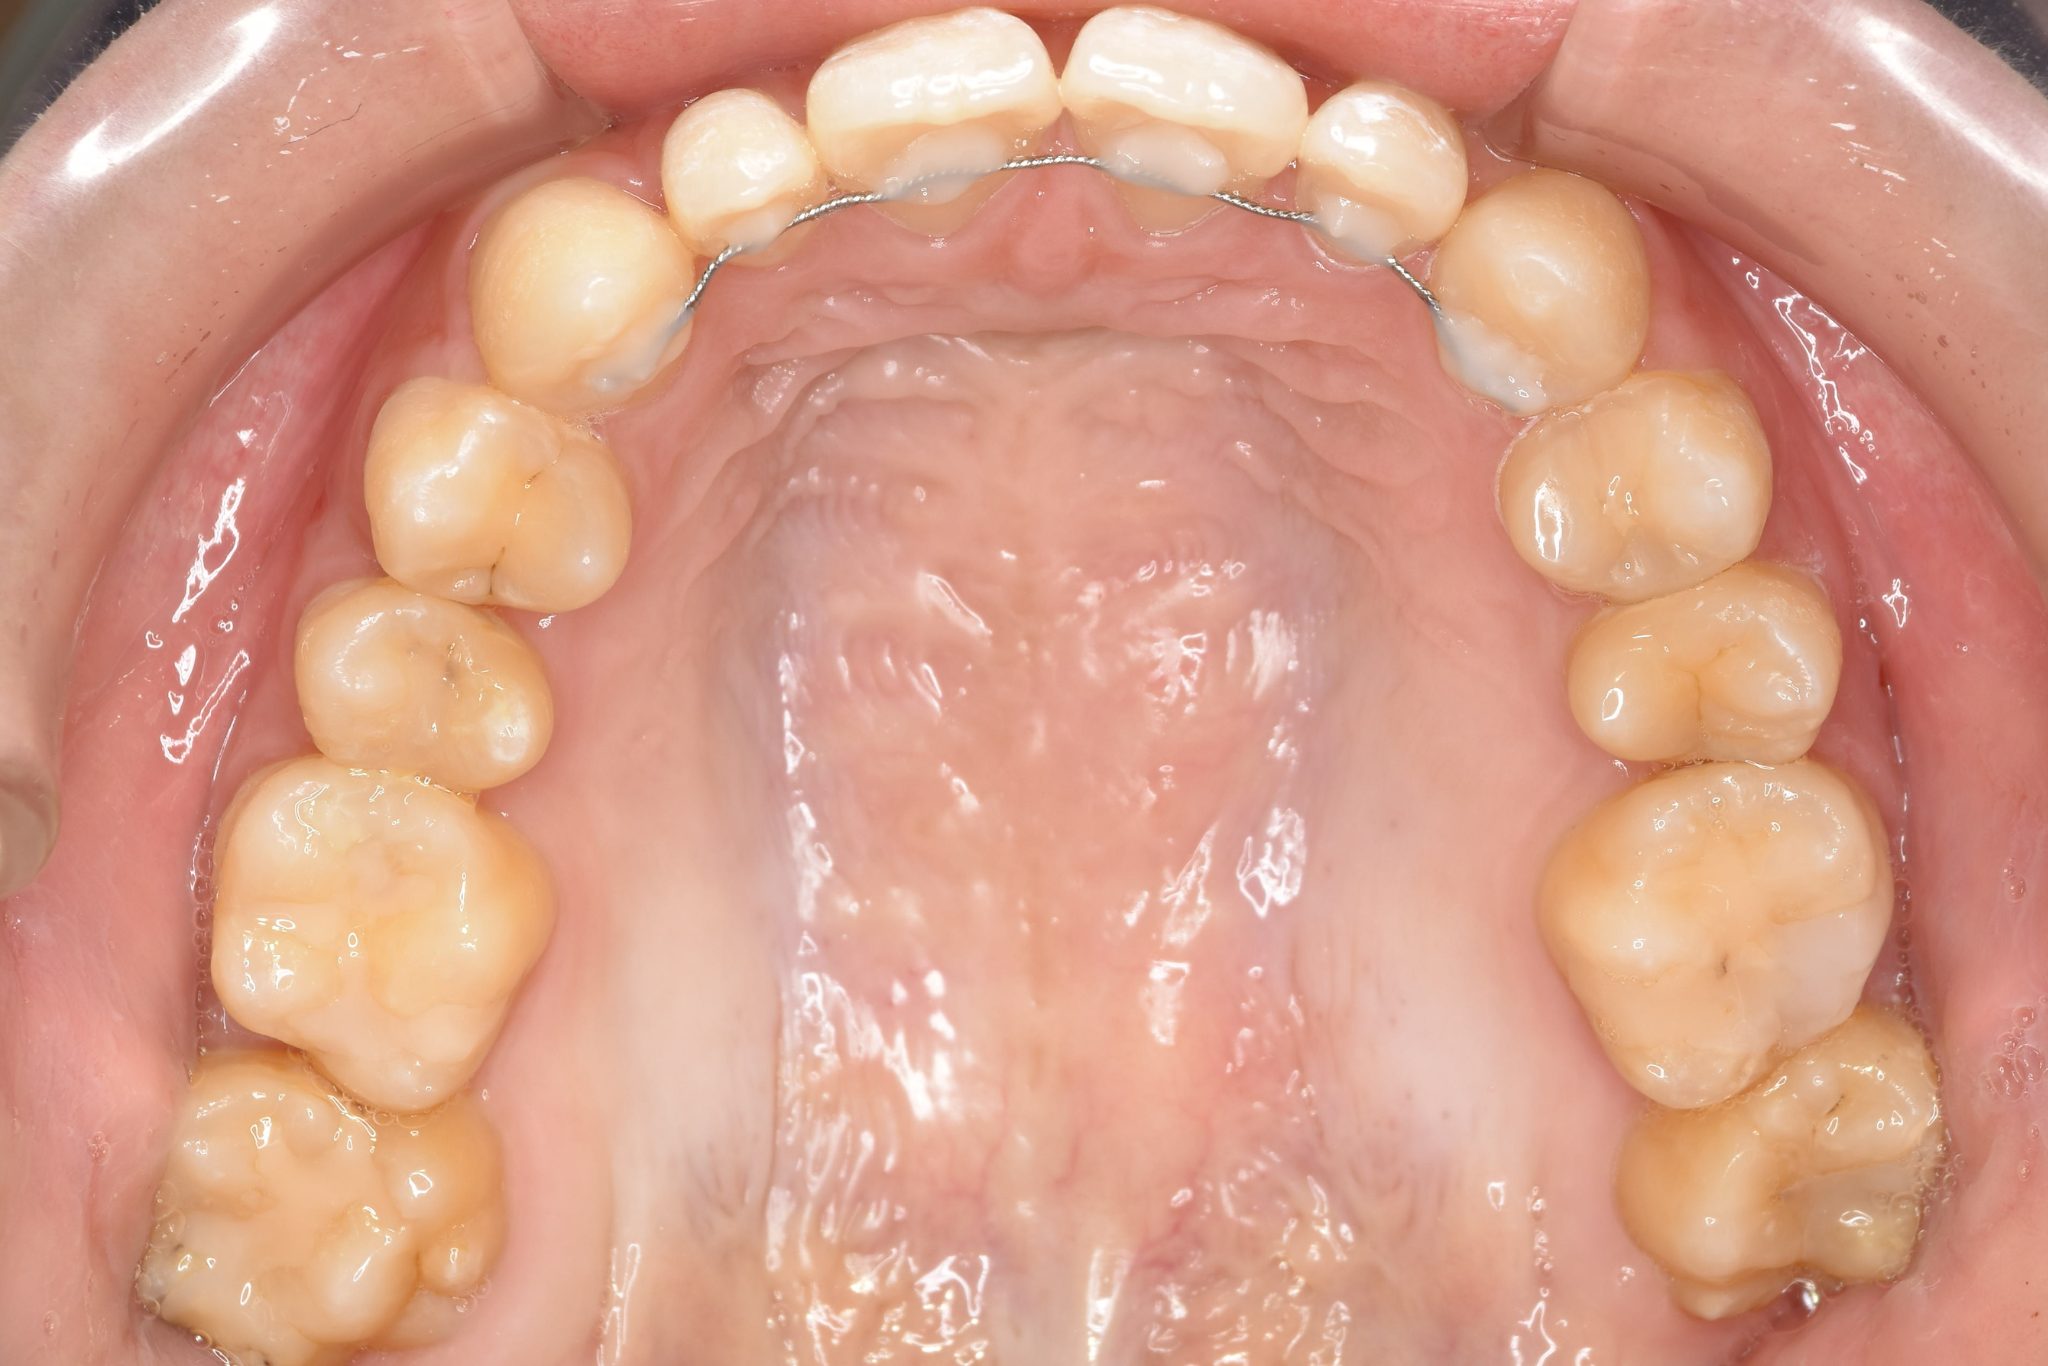

アフター

主訴 歯並び|かみ合わせ

施術内容 MSEと下顎リンガルアーチを用いて上下顎骨を拡大した。

その後マルチブラケット装置を用いて非抜歯で歯牙を配列し良好な咬合を獲得した。

吸指癖と鼻閉症状は改善した。

治癒期間 2年2か月間